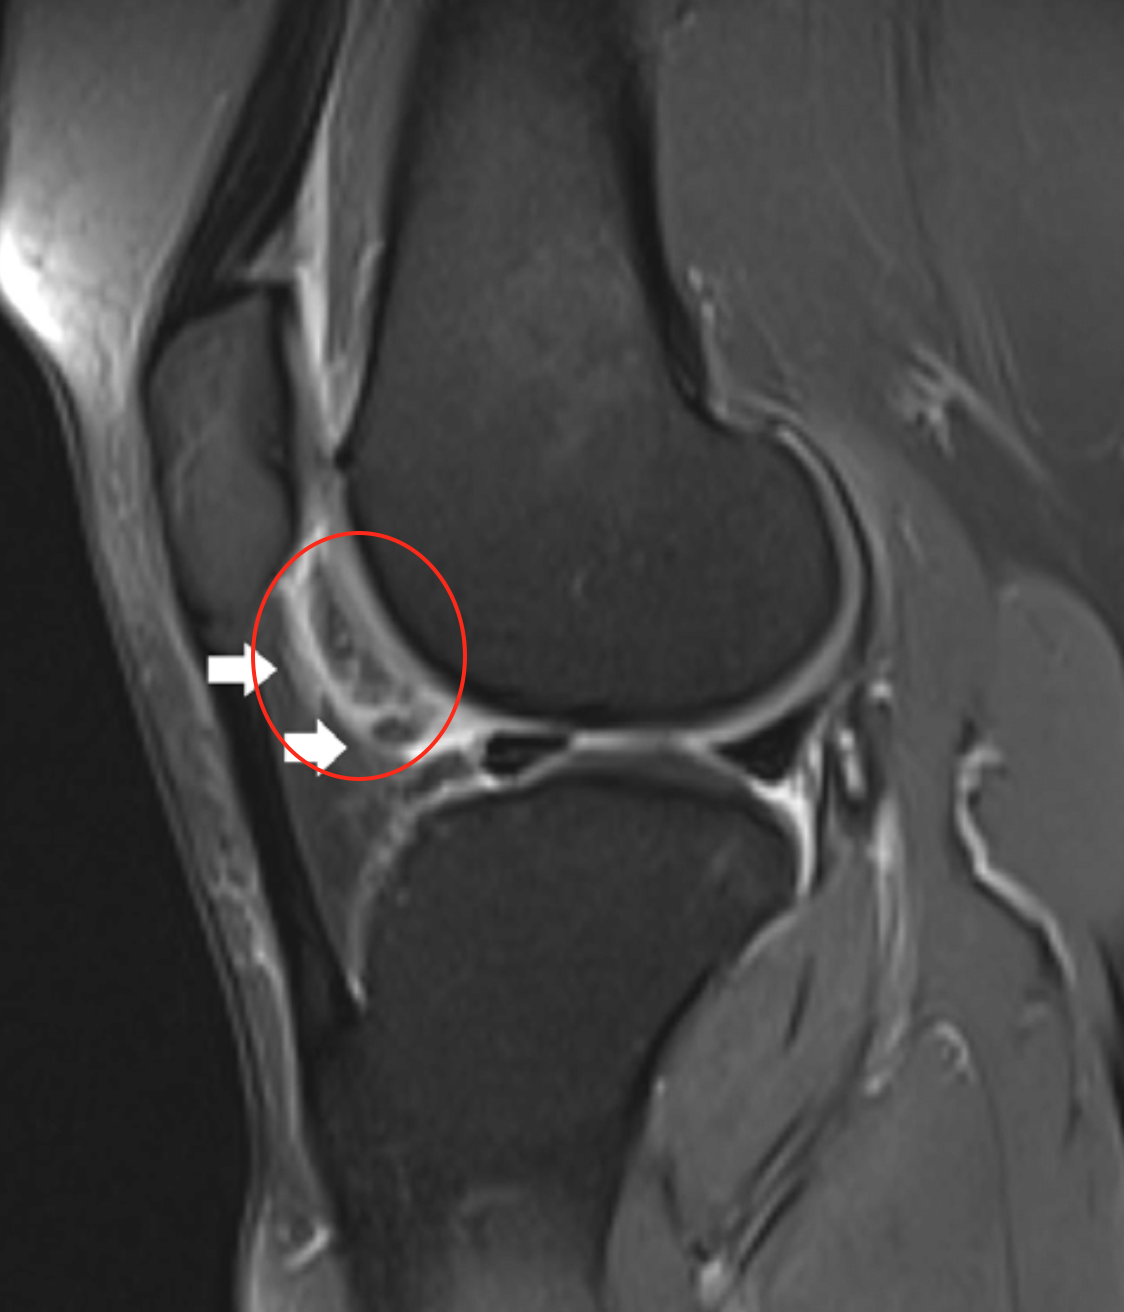

• Ligamentum mucosa injury (red circle)

• Notch sign

• Deepening of the normal groove in the lateral femoral condyle

• > 2mm is diagnostic of acute or chronic tear